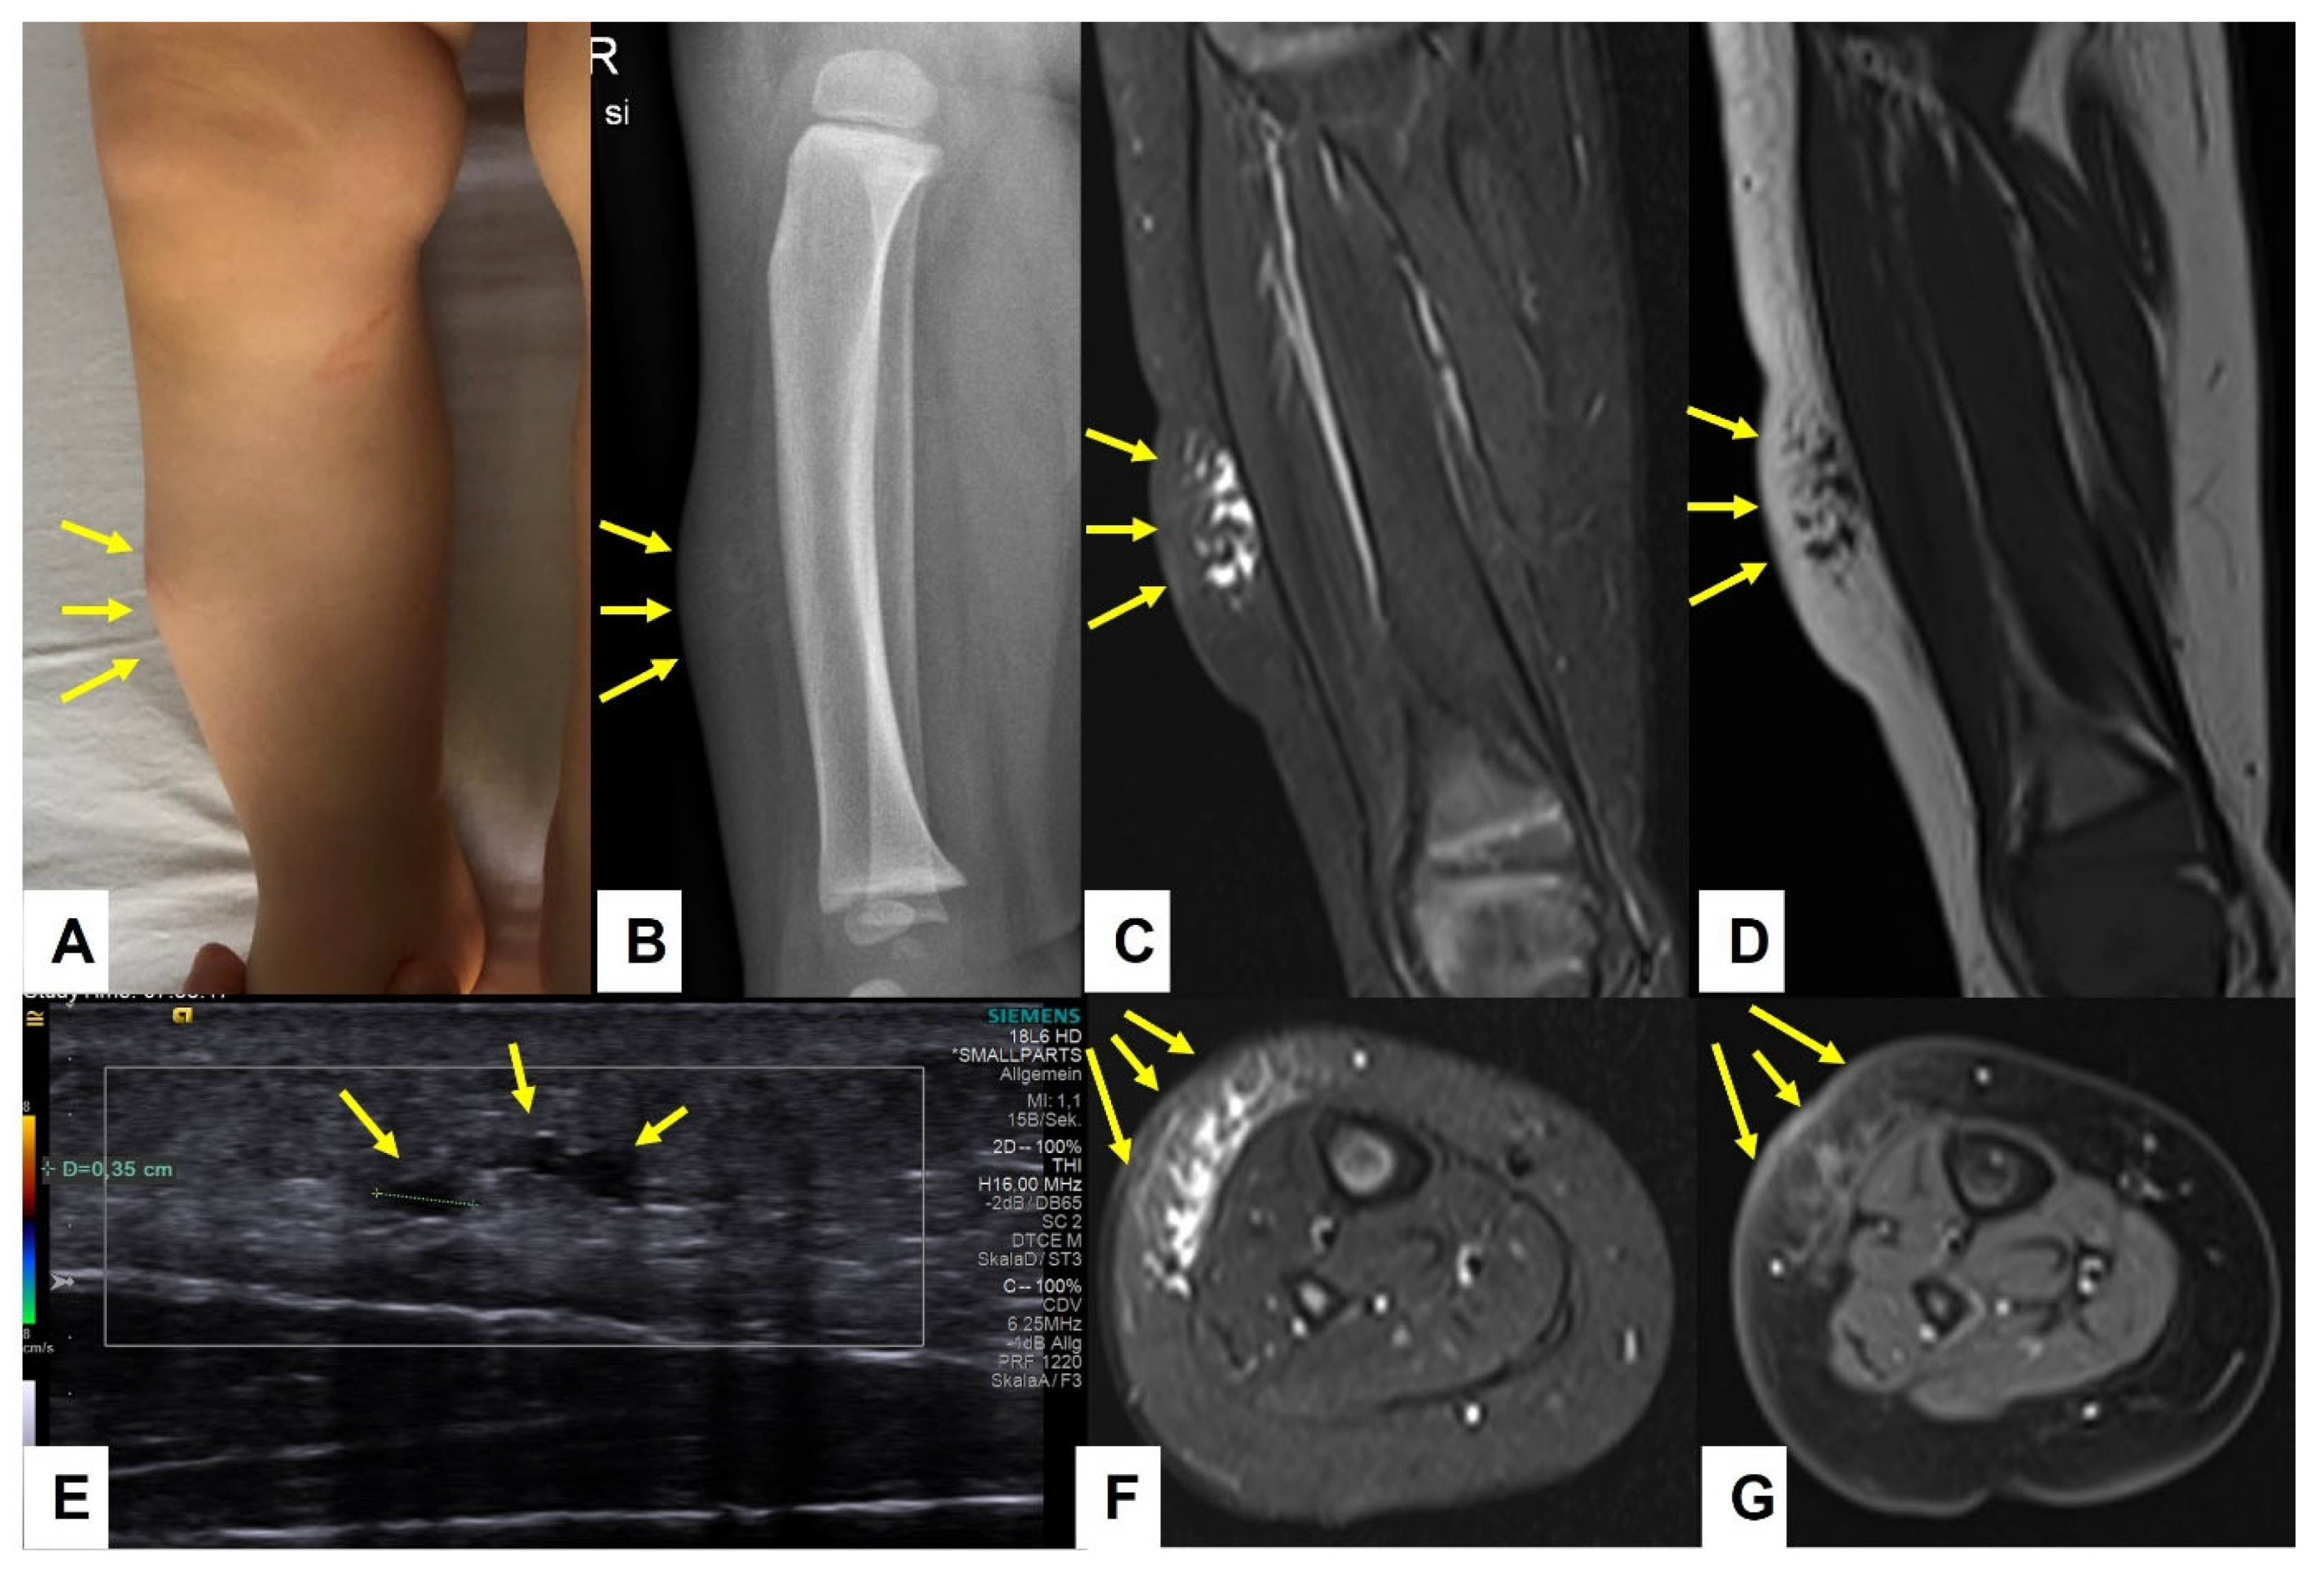

Figure 11.

This composite figure illustrates the typical differences in contrast enhancement between the subcutaneous venous malformations (VM) and subcutaneous granuloma annulare (SGA) during MRI. The lesions are pointed out by yellow arrows. Image (A) depicts the extension of the VM on the medial side of the right upper arm. The lesion cannot be seen during the arterial phase of MR angiography (B). The VM fills slowly at the beginning of the venous phase at 32 s post-contrast application (C) and intensifies at 96 (D) and 120 s (E) post-contrast application. The SGA on the anterior side of the right knee, as depicted in image (F), shows a homogenous enhancement after contrast application which slowly fades away at the end of the examination (G–J).